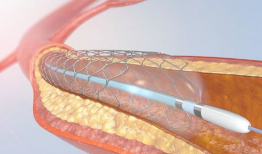

心脏支架手术视频,技术革新与患者康复之路

亲爱的读者,你是否曾好奇过心脏支架手术的全过程?想象当你躺在手术台上,医生们正小心翼翼地为你植入支架,那会是怎样的场景呢?今天,...